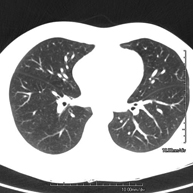

- High resolution Chest CT

Diagnostic test to examine the lung using CT (Computed Tomography) equipment to obtain two- and three-dimensional images, that allow a highly specific anatomical examination of the lung, being able to assess very small anatomical structures. This technique is very important among patients with suspected lung disease.